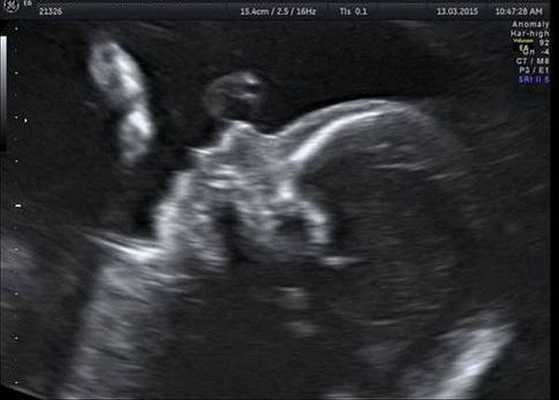

Индивидуальная профилактика синдрома предполагает проведение медико-генетического консультирования семьи и пренатальной ультразвуковой диагностики беременной женщины в установленные сроки [12] .